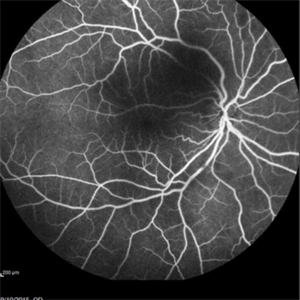

Angiography showed normal vessels posteriorly but severe capillary drop out throughout the periphery OU with scattered severe neovascularization at the edge of the capillary drop out peripherally.

Sickle Cell Retinopathy Sickle Cell RetinopathySep 13 2015 by Thomas A. Ciulla, MD, MBA, FASRS Angiography showed normal vessels posteriorly but severe capillary drop out throughout the periphery OU with scattered severe neovascularization at the edge of the capillary drop out peripherally. Photographer: Thomas Steele Condition/keywords: peripheral retinal neovascularization, sea fan, sickle cell retinopathy